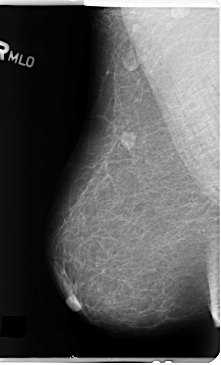

B_3153_1.RIGHT_MLO

RIGHT_MLO LINES 4736 PIXELS_PER_LINE 2872 BITS_PER_PIXEL 12 RESOLUTION 50 NON_OVERLAY